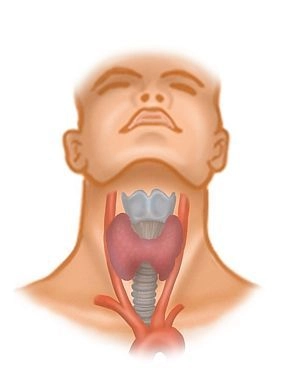

Localizado entre a borda anterior do músculo esternocleidomastóideo, a mandíbula e a fossa jugular, o triângulo anterior do pescoço inclui os músculos supra- e infra-hioideos, vasos, nervos e a glândula tireoide na vizinhança do osso hioide. Para tireoidectomia, entre os músculos infra-hioideos, apenas os localizados medialmente

- músculo esternoióideo (esterno → osso hioide) e abaixo dele o

- músculo esternotireóideo (esterno → cartilagem tireoide da laringe) bem como mais lateralmente o

- músculo omoióideo (escápula → tendão intermediário → osso hioide)

são de significância, pois cobrem parcialmente a glândula tireoide e devem ser retraídos intraoperatoriamente.